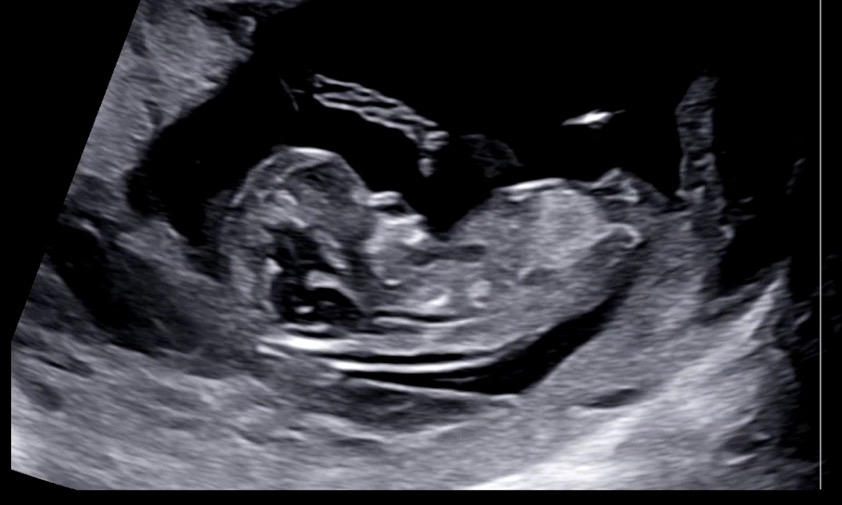

각도법 봐주세요.. ㅎㅎㅎ (12주)

넘 궁금해서 올려봐요 ㅋㅋㅋ 봐주실분~!! 😊